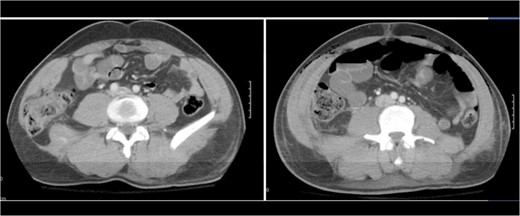

A 43-year-old male patient presented with a right-sided traumatic lumbar hernia after a blunt mechanism. The patient had been pinned between a dirt-mover’s claw arm resulting in a crush mechanism. He sustained injuries to the lumbar spine, sacrum, abdominal wall and 12th rib. On presentation, he did not have clinical or radiographic evidence necessitating abdominal exploration and was observed in a monitored setting. Computed tomography imaging demonstrated a Grynfeltt defect with herniation of the ascending colon and cecum through an area defined by the 12th rib, quadratus lumborum and internal oblique (Figures 1 and 2). After several days of observation and recuperation, the patient continued to have significant pain overlying the hernia site. We electively brought him to the operating room on post-injury Day 4. A laparoscopic repair of the traumatic hernia was performed. Key operative steps included: (i) Wide exposure of the hernia defect via incision of the peritoneum and transversalis as well as mobilization of the ascending colon and duodenal sweep (Figures 3 and 4). (ii) Primary repair of the defect with intra-corporeal suturing of the oblique musculature (Figures 5 and 6). (iii) Placement of an underlay mesh with appropriate redundancy at least 4 cm in all directions around the defect and seating against the iliac crest (Figure 7). Post-operative imaging demonstrates obliteration of the hernia defect and restoration of the abdominal wall (Figures 8 and 9). The patient has recovered, returned to the work force and has no pain or bulge at the repair site 6 months after injury.

Recreation of the abdominal wall contour is seen on the post-operative computed tomography.